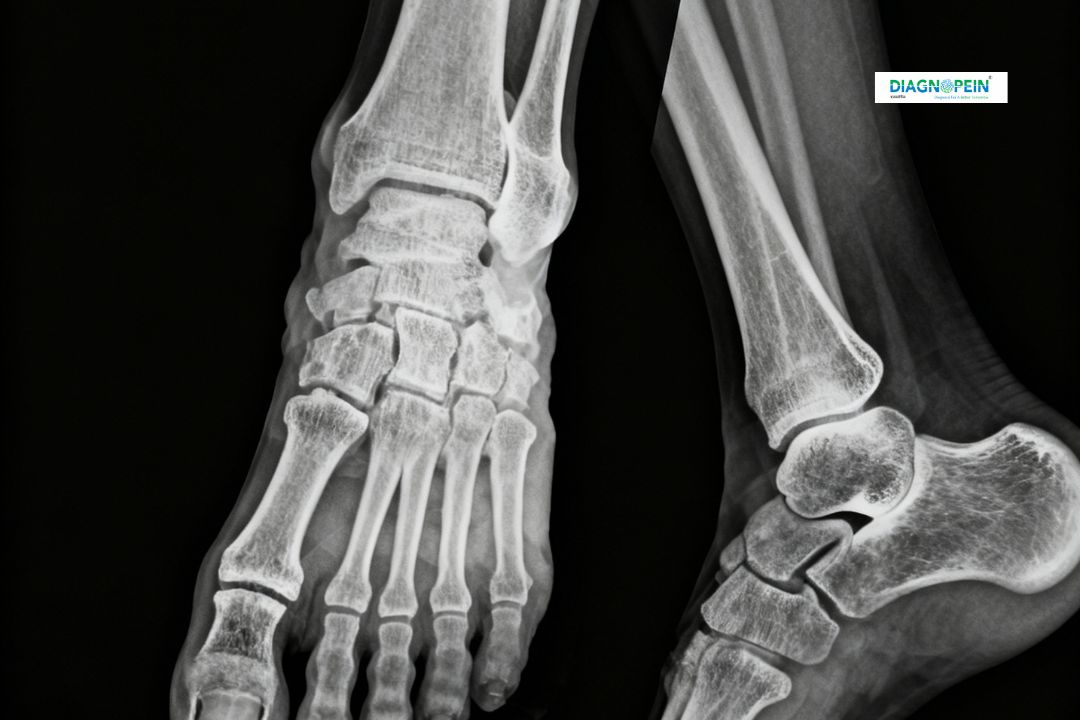

At Diagnopein in Karad, we provide accurate X-Ray Right Foot AP/Oblique imaging to help diagnose bone and joint problems efficiently. This diagnostic test uses low-dose X-rays to create detailed images of the right foot in anteroposterior (AP) and oblique views, allowing doctors to assess fractures, dislocations, deformities, or bone infections.

An X-Ray of the right foot in AP and Oblique views is crucial for identifying underlying injuries or conditions affecting the bones, joints, and soft tissues of the foot.

It provides a complete visual assessment of the metatarsal bones, ankle joints, and surrounding structures from two angles, helping physicians to:

2. Positioning: The patient must place the right foot on the X-ray plate. For the AP view, the X-ray beam passes from the front to the back of the foot. For the Oblique view, the foot is angled slightly to visualize bones and joints more clearly.

3. Imaging: The technologist captures two images – one AP and one Oblique, using a low radiation dose.

1. Views Taken: AP (Anteroposterior) and Oblique

2. Purpose: Evaluation of fractures, deformities, joint integrity, and bone lesions